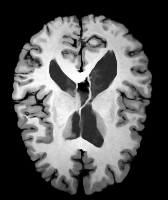

Moving Target Mono-0 Mono-21 DA-1 DA-21 Mono-65 Refer to caption Refer to caption Refer to caption Refer to caption Refer to caption Refer to caption Refer to caption Refer to caption Refer to caption Refer to caption Refer to caption Refer to caption Refer to caption Refer to caption

Image Manual Seg DA-1 Mono-5 DA-5 Mono-200 Refer to caption Refer to caption Refer to caption Refer to caption Refer to caption Refer to caption

Figure 4: Examples of brain MRI registration (top) and knee MRI segmentation (bottom) results. Top: The first two columns are the moving image/segmentation and the target image/segmentation followed by the warped moving images/segmentations by different models. Bottom left to right: original image, manual segmentation, and predictions of various models. Mono-i𝑖i and DA-i𝑖i represent the mono- and DA models trained with i𝑖i manual segmentations respectively.